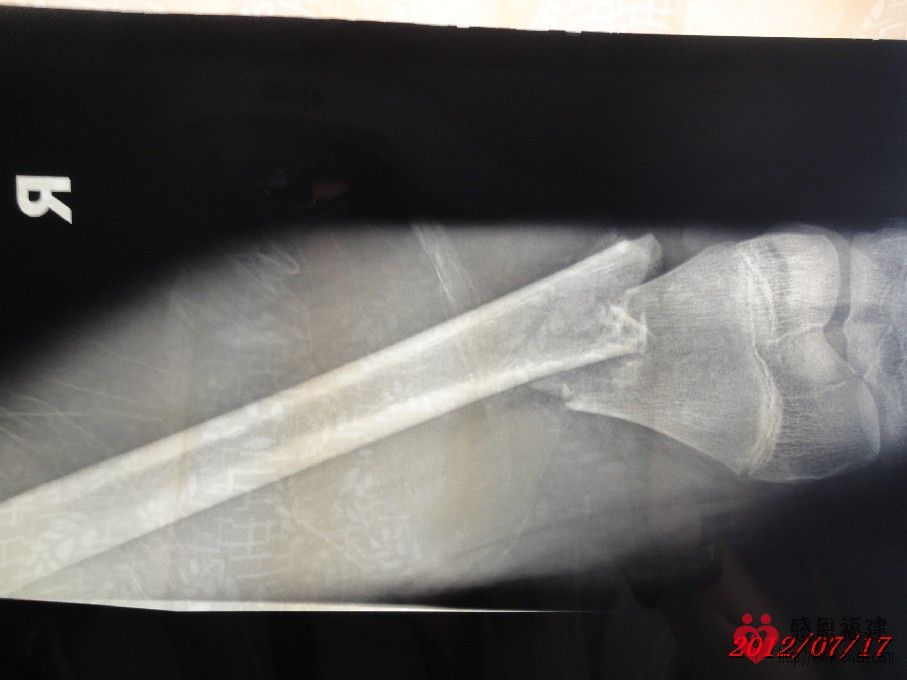

1、事故情况:2012年7月1日14:30左右,智在同学骑邻居的无牌照XGJ125摩托车载着两个同学在北洋小学附近的123县道与停在路旁的无牌照货车发生碰撞(据孩子介绍货车基本占了半边马路,当时对面刚好有车驶来,智在为了避免和对面车发生碰撞往右避让,结果撞上了停在路旁的货车的左后角),导致摩托车撞坏、智在右大腿骨折和另外一位同学大腿骨折。

2、住院情况:事故发生后家人将智在送往闽清县医院治疗,医院同意住院并可安排第二天手术;但智在是一家四口中唯一没有残疾的(由于残疾的父亲在医院照顾智在,哑巴的母亲精神不好还时常跑回老家又不会照顾人,导致眼睛残疾的小弟弟几天没吃上两顿饭),家人和亲戚为了智在治疗后不留下后遗症,最后决定送往福州市第二医院治疗,并于当晚存了2,000元住院费并办好住院手续。但由于家境贫寒,智在的父亲和亲戚到处借债(有的500,有的1,000……),好不容易东拼西凑才筹集到手术费用(现在已经累计存入医院38,000元),手术于7月11日进行,效果还比较理想,但出院时间待定。